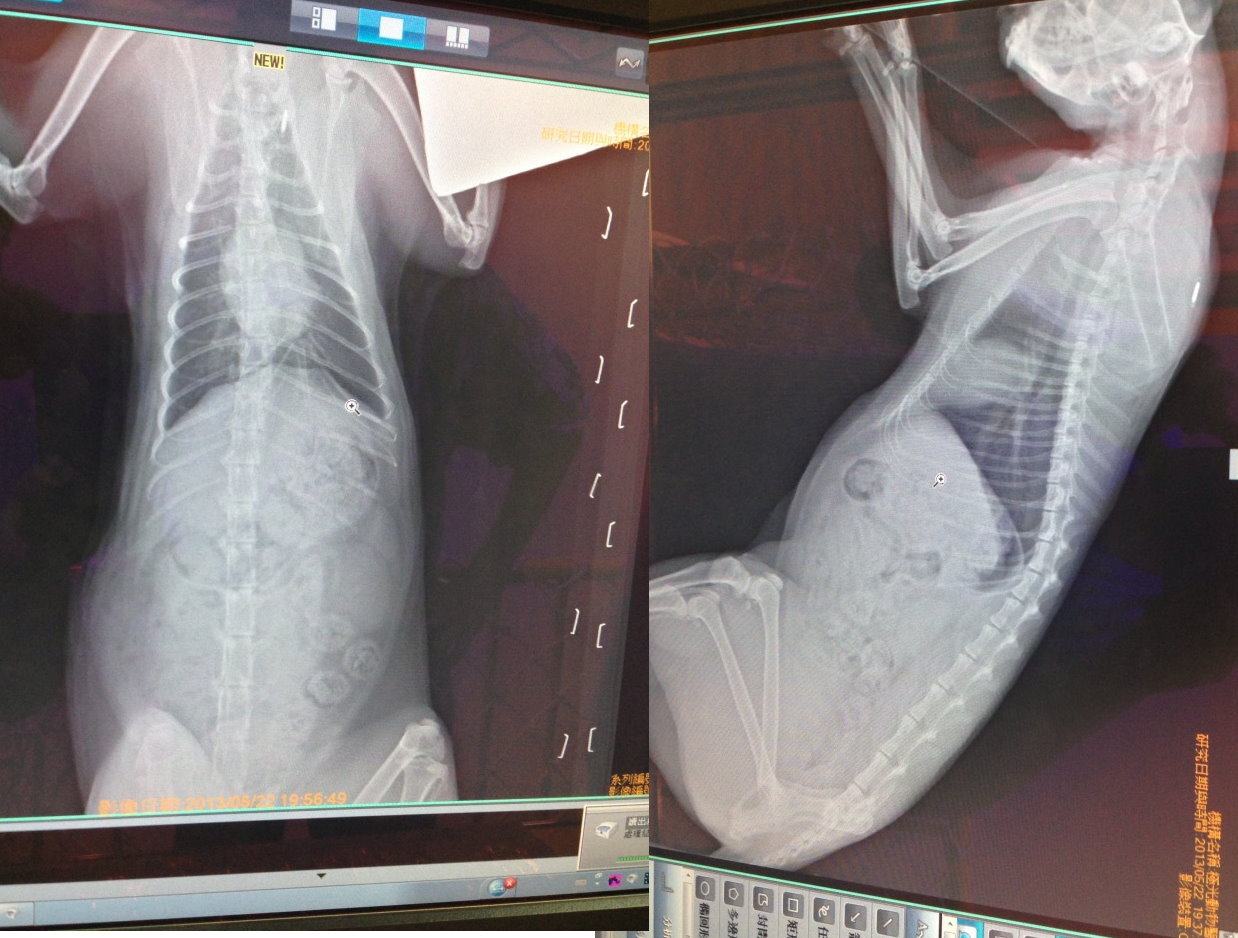

主題: 松江市場爆眼橘貓 申請者姓名: 蔡葦澄 花色: 申請日期: 2013-06-10 12:14:41 申請者部落格: 申請者臉書網址: 所在縣市/合作醫院: 台北市/其他院所醫助專案(醫院請先MAIL溝通) 治療費用: 24885元 需求人數: 26人 已結案 (2013-08-06 13:58:40) 報名人員: vivi cat(已付款)、Susanna Chueh(已付款)、周小蕾(已付款)、kayu x2(已付款)、vivian(已付款)、catannchen x2(已付款)、hiroko(已付款)、坑長(已付款)、Crystal(已付款)、鍾艾霖(已付款)、Fei Lika Tsai(已付款)、小麥(已付款)、Gina(已付款)、Mei Hsien Liu(已付款)、翅膀(已付款)、Amy(已付款)、ifan(已付款)、K、K、K、K、小珍 x3(已付款)、布萊梅樂隊(已付款)、Micky Yang(已付款)、林艾蓁(已付款)、Cecilia Hsu(已付款)、 候補人員: 動物病情說明: 昨天接到松江市場愛心媽媽林大姐來電說有貓咪受困四樓頂,送誘捕籠過去時在附近發現這隻橘子貓眼睛怪異明顯凸起,放置誘捕籠,沒想到貓咪進去吃完罐頭全身而退,趕緊跑回去換另一種誘捕籠,回到現場貓卻已經消失,今天再過去,遠遠就看見一群貓聚集,另一個愛心媽媽在餵食,放置誘捕籠,其他已經結紮剪耳的貓咪一直要往裡面鑽,小橘又很怕生躲遠遠,很害怕其他貓咪進去後,小橘會有警戒,折騰一會橘橘總算進去,緊急送往醫院,眼睛出血,後腳淋巴腫大,腳輕微破皮,眼睛恐怕是保不住。

因為眼球凸出失去視力,眼睛無法閉合,造成眼睛乾澀有很多分泌物,最後決定摘除眼球減輕貓咪負擔,該眼睛應該早就沒有視力,摘除後貓咪恢復狀況很好,沒有任何適應上的問題,眼睛以後都可以很乾爽,等完全恢復後會R回交由愛心媽媽照顧。